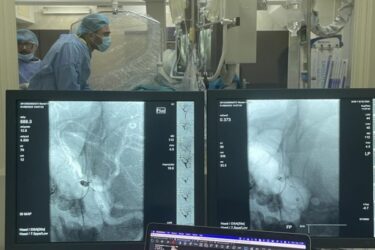

O echipă multidisciplinară de la Institutul de Medicină Urgentă, formată din neurochirurgi și chirurgi endovasculari, a salvat viața unui pacient de 27 de ani, diagnosticat cu hemoragie subarahnoidiană, cauzată de un anevrism rupt de artera comunicantă anterioară. Anevrismul cerebral reprezintă dilatarea unui vas de sânge […]